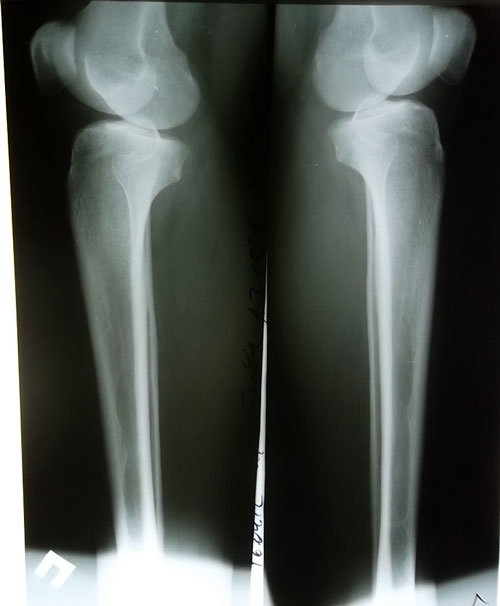

Диагноз: О-образная деформация нижних конечностей, ротация справа.

Вид операции: кортикотомия б/б кости верхней трети, наложение шарнирного коррекционного де ротационного аппарата Илизарова - Онипко.Рентген до операции, прямая проекция.Рентген до операции, боковая проекция.

Рентгеновские снимки от 24.07.2012г.прямая проекциябоковая проекция